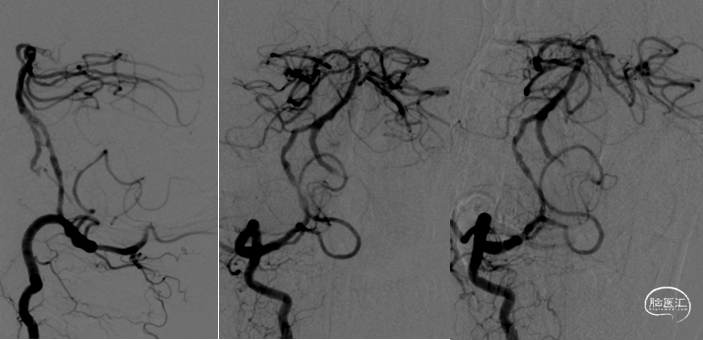

全麻后,股动脉置入6F血管鞘,6F导引导管配合超滑导丝至右侧锁骨下动脉建立通路,Synchro-14(200cm)微导丝配合4mm×30mm快交球囊定位V1狭窄扩张。

6F导引导管进入V2后,Synchro-14 (200cm)微导丝配合Gateway 2.5mm×9mm球囊先后进行基底动脉、椎动脉V4段狭窄扩张。

撤出球囊后,Synchro-14(200cm)微导丝配合XT-27至基底动脉远端,从远至近分别置入Neuroform EZ 3mm×15mm及Neuroform EZ 3.5mm×20mm支架。

最后保留微导丝在椎动脉内,将导引导管退至锁骨下动脉后,送入5mm×19mm球扩式支架并释放。

300cm微导丝携Gateway球囊到位,行球囊扩张及预扩张后造影。